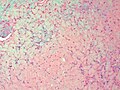

Chondromyxoid fibroma. H&E stain. | |

| LM | spindle cells or stellate cells in a myxoid or chondroid stroma, lobules with hypocellular centers and hypercellular peripheries, +/-giant cells in the hypercellular periphery, scattered calcifications, no true hyaline cartilage formation, no mitotic activity |

Features:[3]

- Spindle cells or stellate cells in a myxoid or chondroid stroma.

- Lobules with hypocellular centers and hypercellular peripheries.

- Giant cells in the hypercellular periphery.

- Scattered calcifications.

- No true hyaline cartilage formation.

- No mitotic activity.